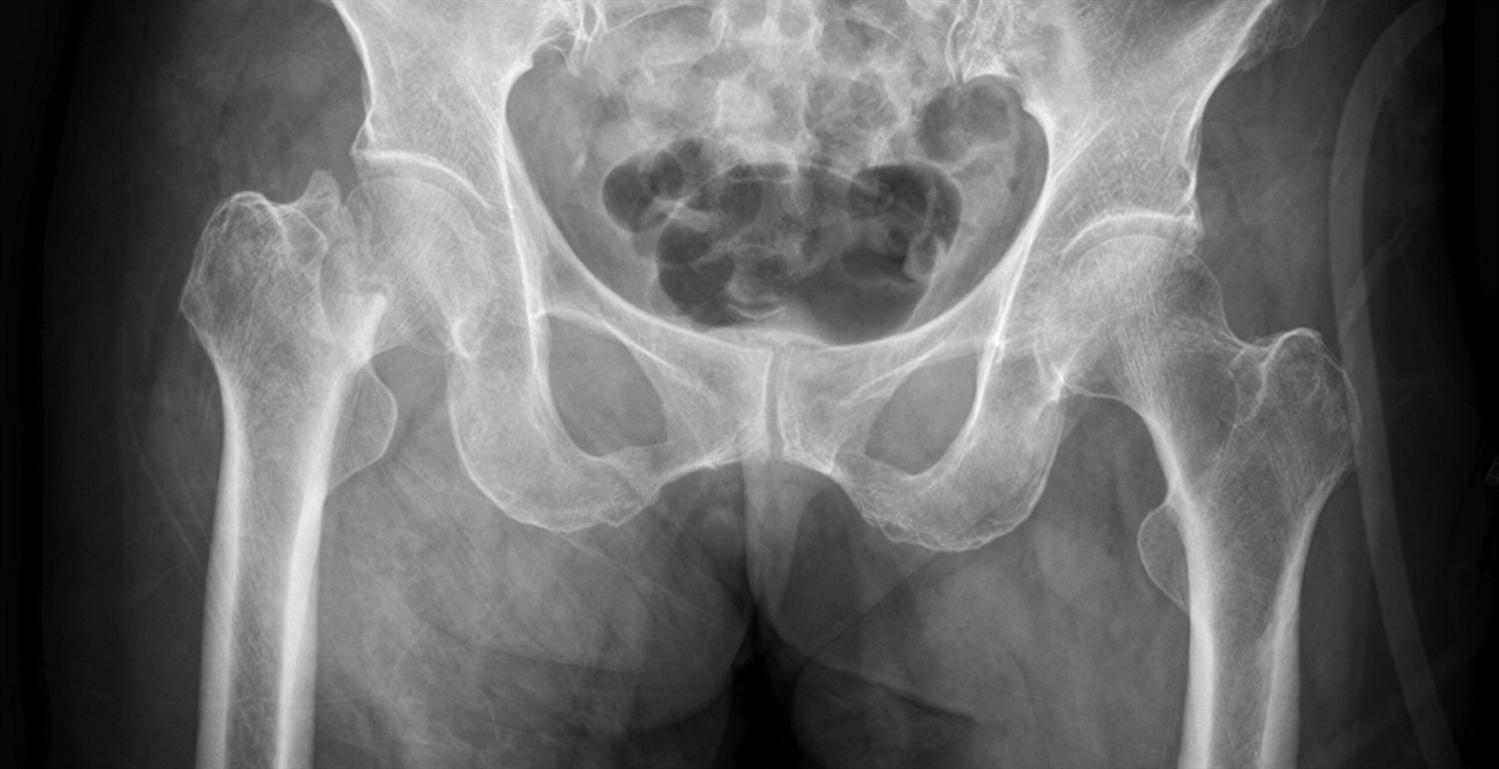

Displaced stress fracture of the femoral neck in young active adults

Is Femoral Neck Fracture Serious . Femoral neck fractures are common injuries to the proximal femur associated with increased risk of avascular necrosis, and high levels of patient morbidity and. If a femoral neck fracture is left untreated, an interruption of blood flow to the femoral head can occur (called avascular necrosis). This region is prone to fractures, particularly in the elderly population due to. It can cut off the blood supply to the head of the thighbone. A femoral neck fracture can be particularly serious because of a possible complication: Some of these fractures represent a dilemma for. A femoral neck fracture can be accompanied by damage to the cartilage, ligaments and joint surfaces in the hip joint and. The femoral neck is a crucial part of the femur, connecting the femoral head to the femoral shaft.